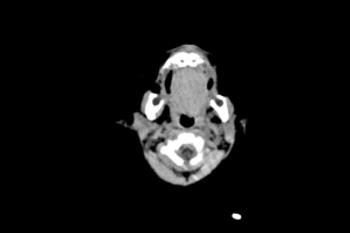

Figure 4. Images obtained in the case of an 18-year-old woman, first seen for rash at 10 weeks of pregnancy, with confirmed Zika virus infection. US findings obtained at 20 weeks of gestational age were reportedly normal, with normal head circumference of 17.5 cm. At 37 weeks of gestational age, (a) sagittal transvaginal and (b) coronal transabdominal US images obtained with the head upside down show a small head circumference (26.4 cm, corresponding to 28 weeks 5 days, below the 3rd percentile), moderate ventriculomegaly with dense intracranial calcifications (arrowheads on a), and abnormal head shape with flattened appearance and thickened skin (arrow on a). On the sonogram, it is difficult to precisely localize the calcifications, given the thin parenchyma. (c, d) Axial bone window CT images, (e) sagittal localizer CT image, and (f–h) axial CT images show microcephaly with cerebral atrophy, and, despite ventriculomegaly, the extra-axial cerebrospinal fluid spaces are still prominent. The hypoattenuating calcifications are predominantly located in the subcortical white matter at the gray matter–white matter interface. There is markedly abnormal skull shape with some eversion of the bones at the suture sites (particularly frontoparietal sites), with redundant skin folds (particularly in the parieto-occipital region). (i) Sagittal T1-weighted, (j, k) coronal T2-weighted, and (l) axial susceptibility-weighted MR images obtained at 1 month of age show an undersegmented midbrain, severe microcephaly, open sylvian fissures, and polymicrogyria. The dense calcifications are evident on the susceptibility-weighted image. On the sagittal images (a, e, i), note the small supratentorial compartment and associated skull deformity.

Figure 6. Images obtained in the case of a 24-year-old woman pregnant with twins, with characteristic rash at 9 weeks of pregnancy and confirmed Zika virus infection. (For each pair of images, the first image is of twin A, and the second image is of twin B.) At 14 weeks of gestational age, the fetal head size of both twins was normal. The head size never went below the 3rd percentile for either fetus in examinations at 19–28 weeks. (a, b) Sagittal and (c, d) axial fetal MR images were obtained at 36 weeks. (e, f) Axial and (g, h) surface reconstruction postnatal CT images and (i, j) axial T2-weighted and (k, l) coronal MR images were obtained 1 week after delivery at 38 weeks of gestational age. There is severe microcephaly with profound frontal lobe hypoplasia. Calcifications in the subcortical white matter at the gray matter–white matter junction are visualized. Both twins have a flattened appearance of the pons. The spinal cord is atrophic (best seen on a). Redundant skin is seen in the occipital region. There is polymicrogyria involving the frontal and parietal regions and atrophic cortex and white matter in the occipital regions. Each twin has hypoplasia of the corpus callosum, with prominent fornices. There is abnormal myelination in the occipital region that, in twin A (i), has the appearance of a cyst or septation within the ventricle. The cerebellum is somewhat small and nodular. There is lack of rotation of the hippocampi.